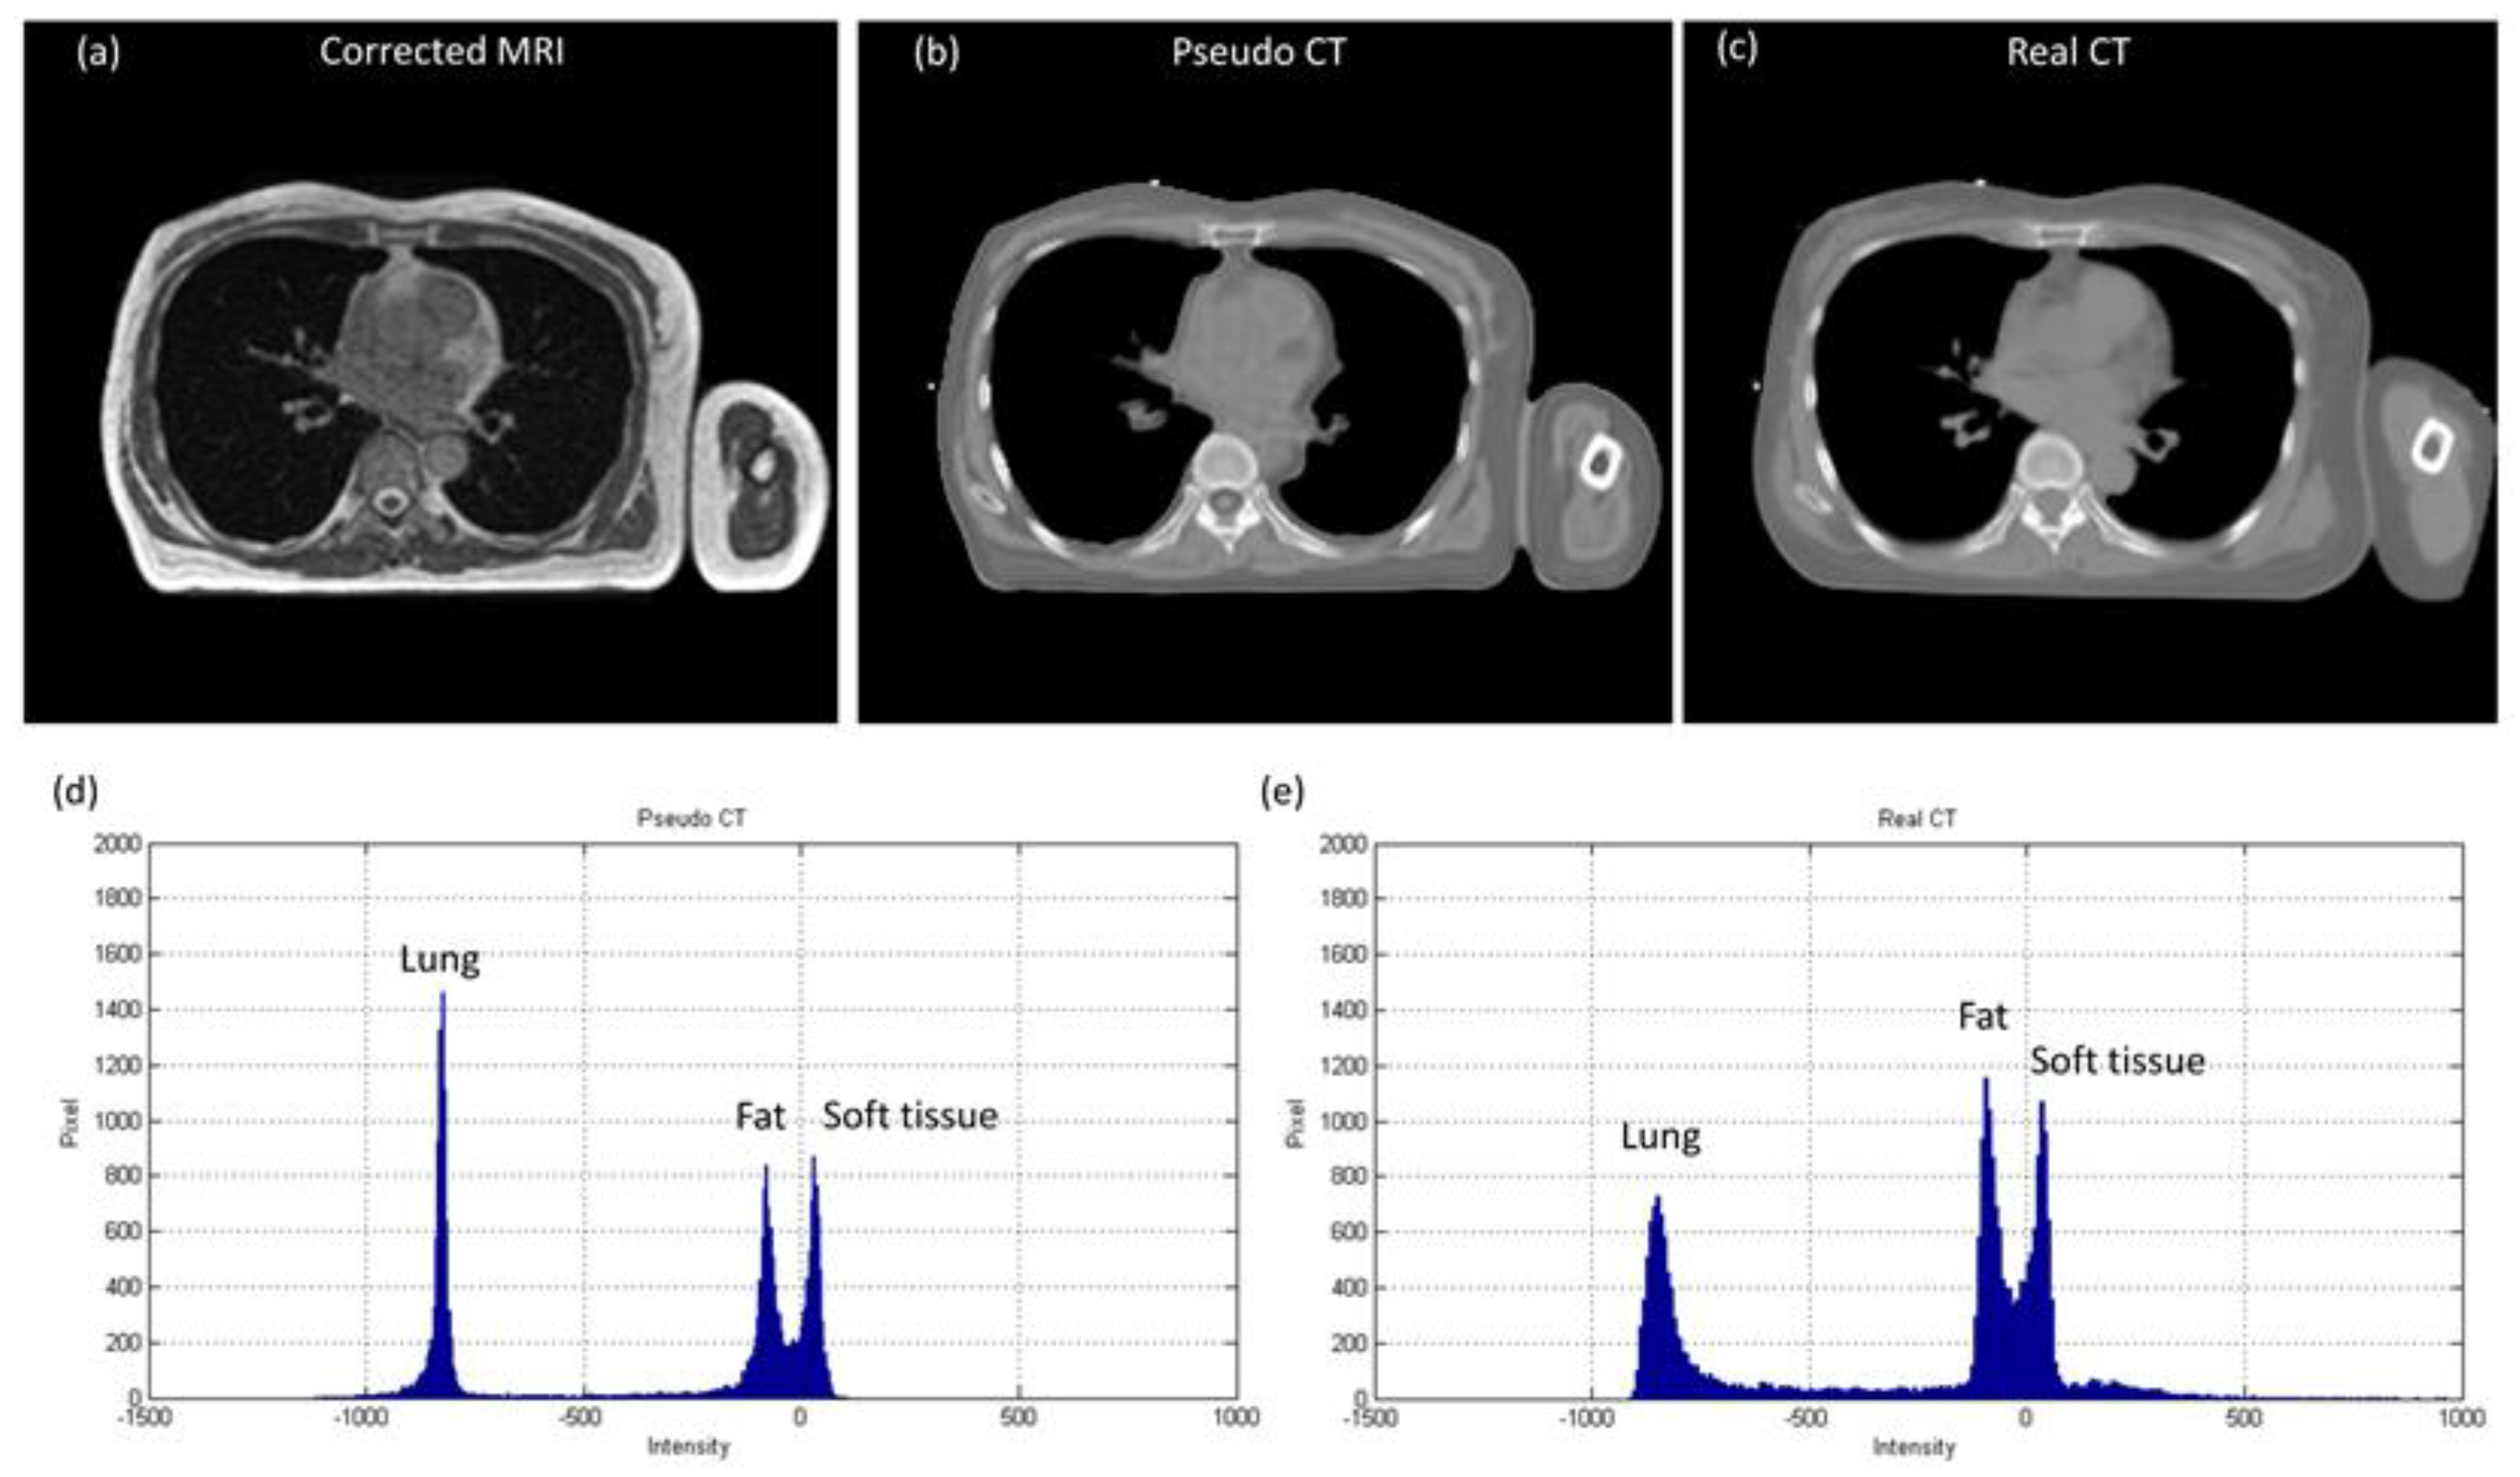

3.2. Abdominal Imaging for Lesion Detection